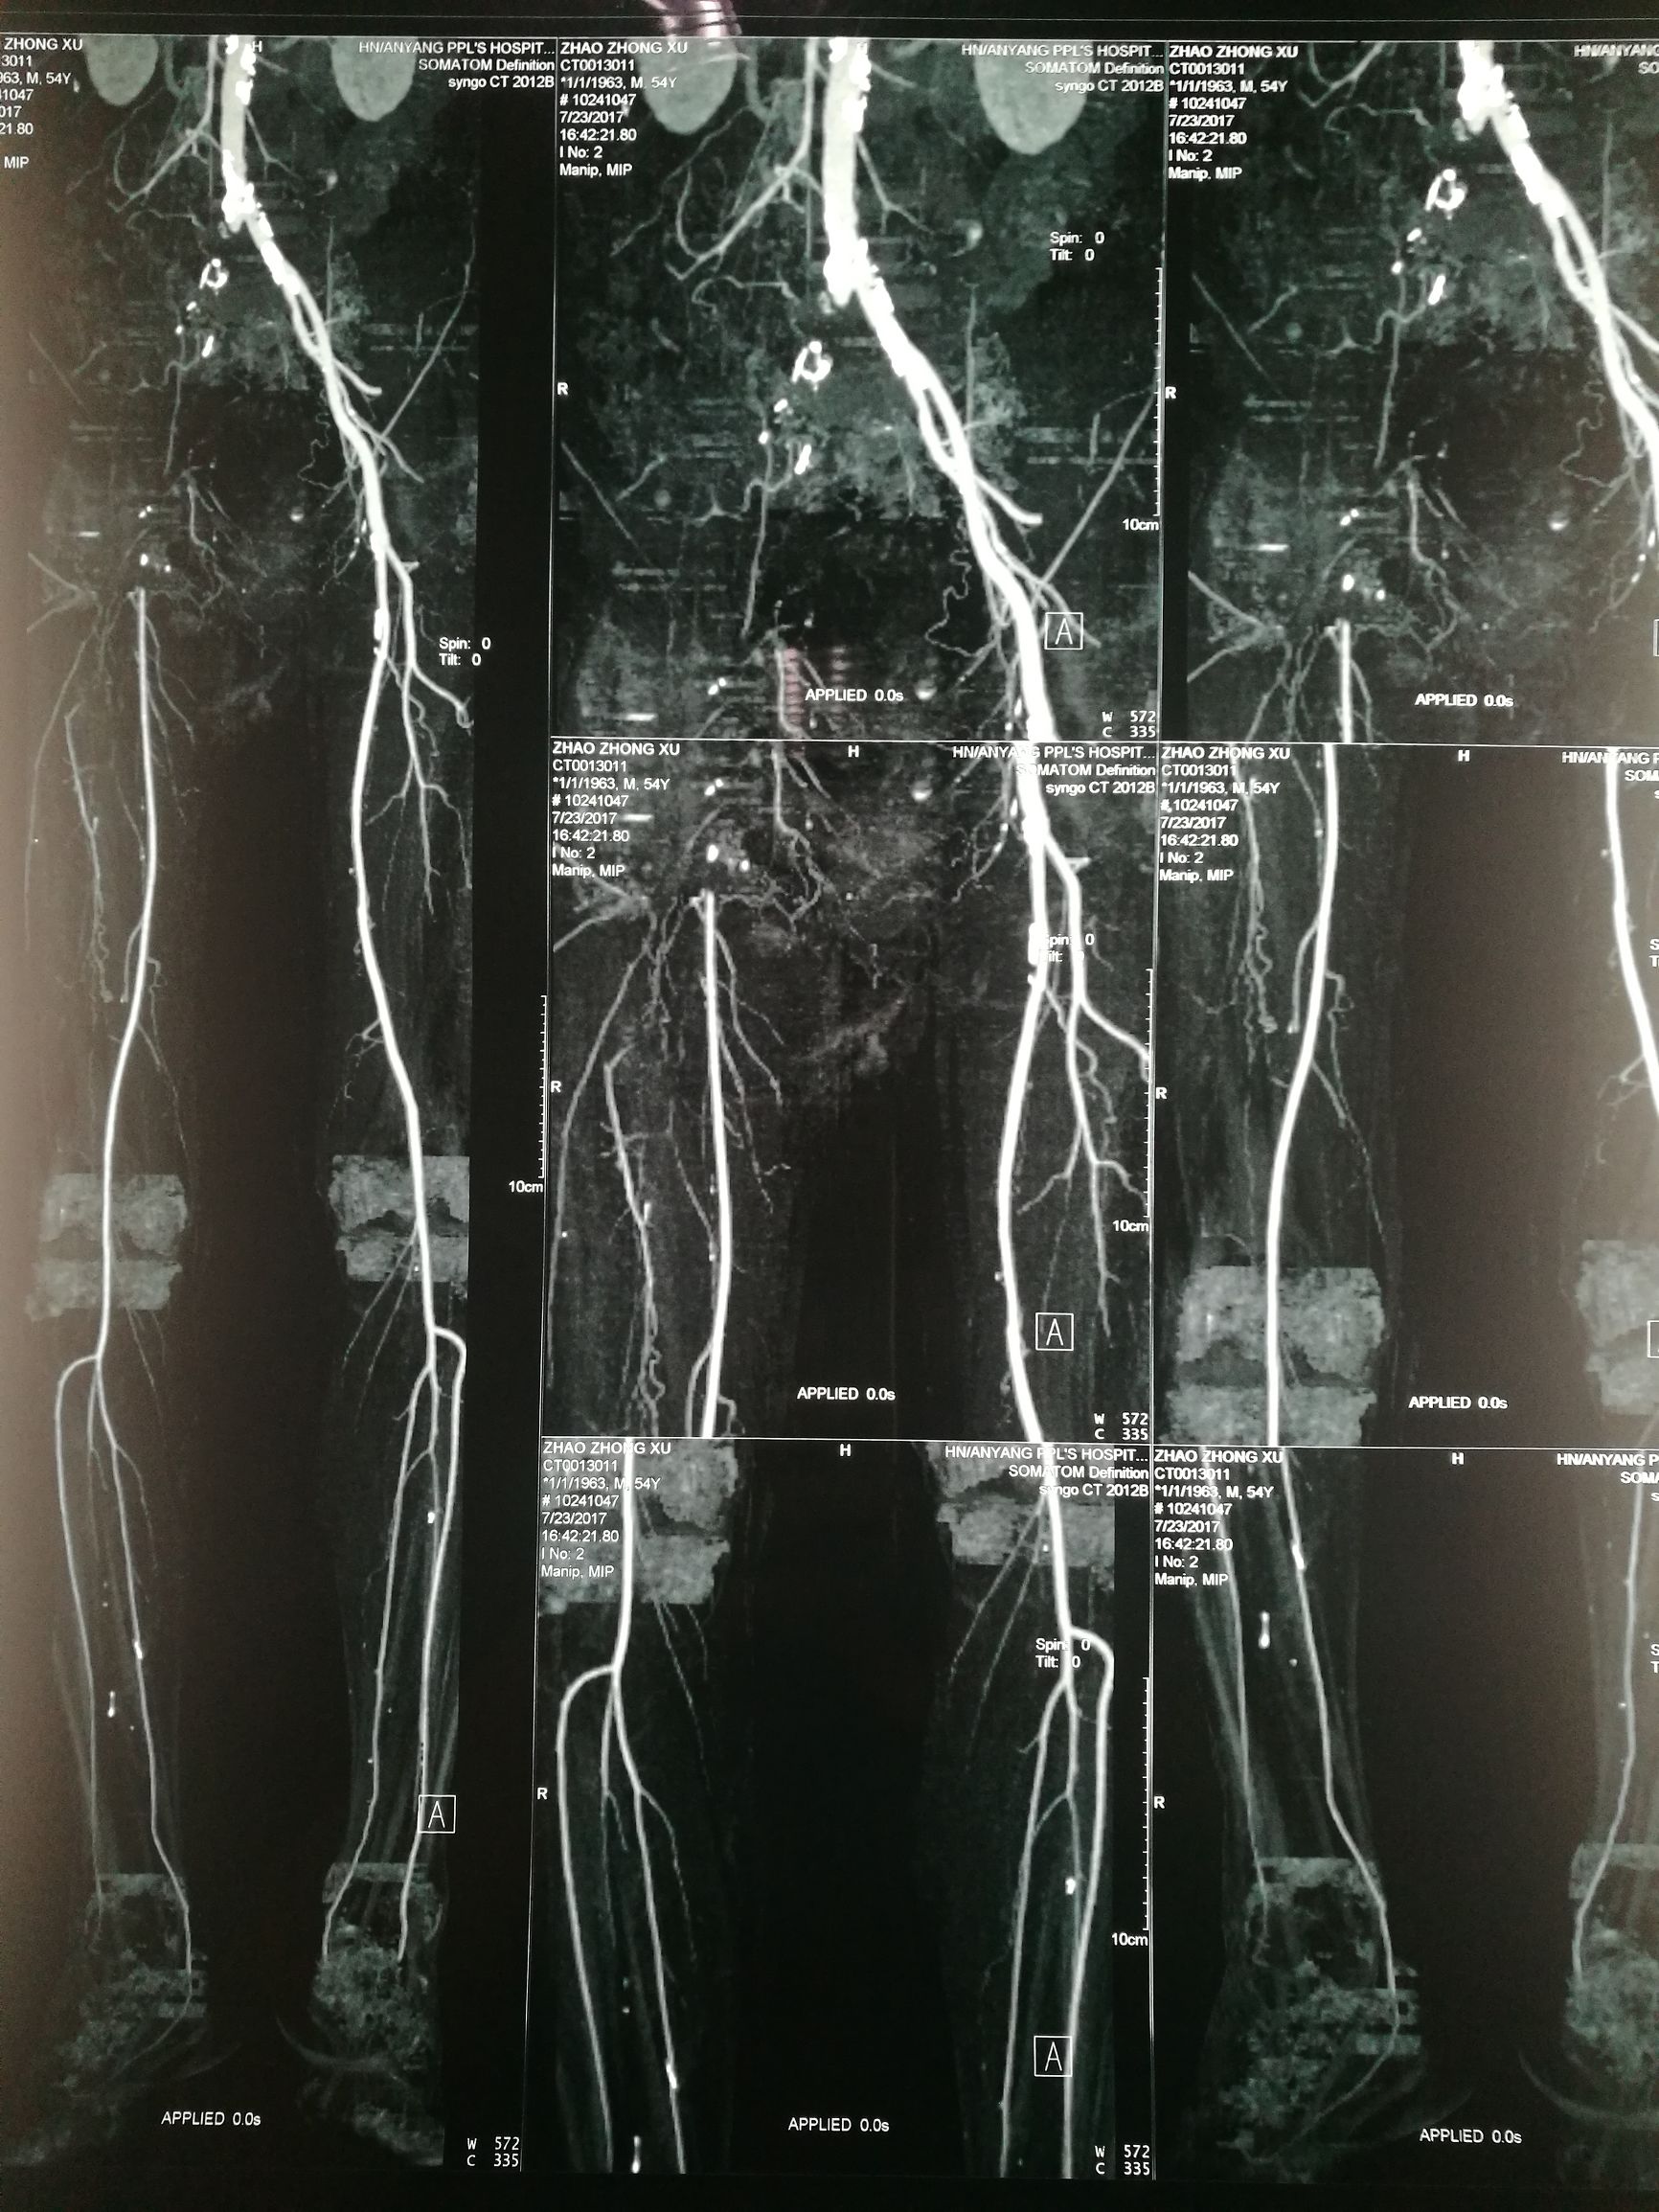

54岁男性,右足疼痛半月余。患者半月前无明显诱因突发右下肢疼痛,行走后加重,休息减轻。超声提示腹主动脉左髂动脉多发狭窄闭塞,右髂动静脉闭塞。CTA

对比正常解剖模式图,我们可以发现:右侧髂总髂内髂外股总动脉未显影,股深动脉未显影,右侧股浅动脉起始段未见显影,考虑有血栓闭塞的可能。